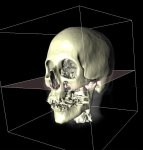

Screenshots

|

|

|

| YaDiV Hauptfenster | Region of Interest | Segmentierung |

|

|

|

| 2D Segmentvisualierung | 3D Segmentvisualierung | Marching Cube |

|

|

|

| Pseudo-Color Darstellung | Settings Browser | DICOM File Info Window |